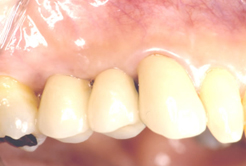

インプラント治療の前に(骨の環境整備)右上小臼歯部

右上小臼歯部

- インプラント(2本)

- 骨造成(GBR)

- 審美歯周外科

- インプラント上部セラミック冠 (2本)

- 天然歯セラミック冠(1本)